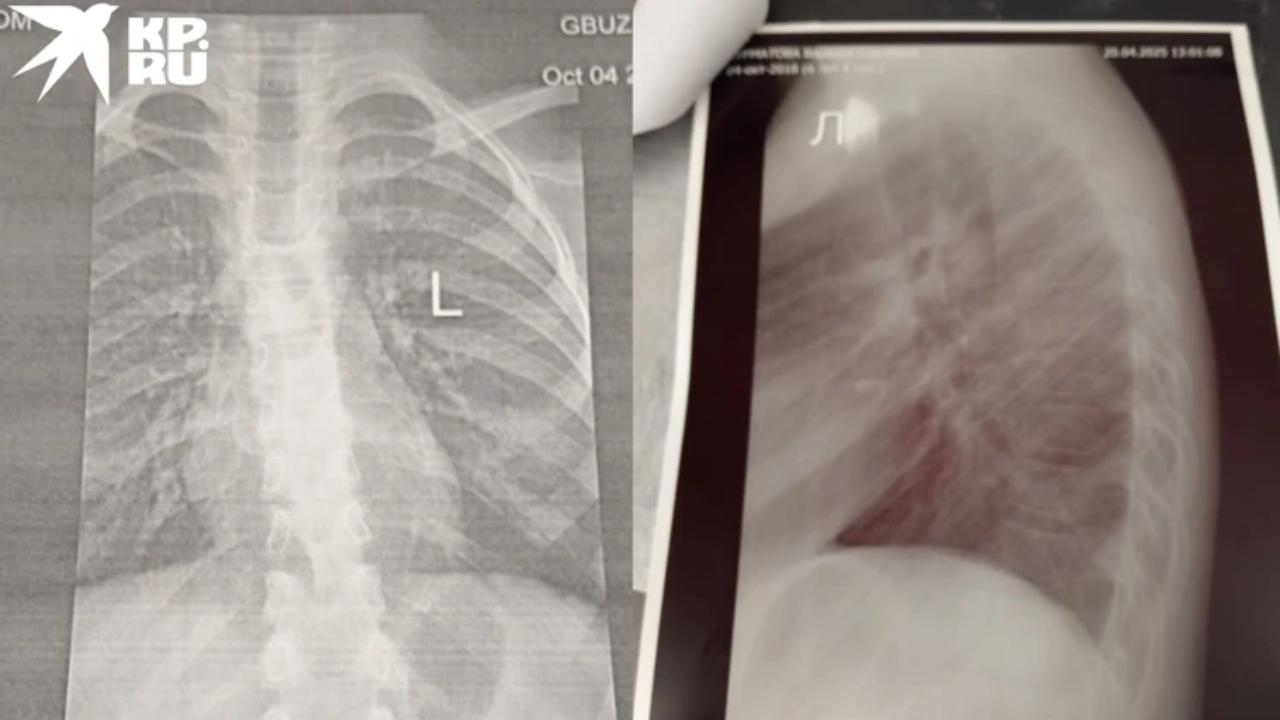

Врачи диагностировали у потерпевшей компрессионный перелом шести позвонков. Она провела пять дней в больнице и вышла из неё в корсете. Ей назначили постельный режим и реабилитацию, включающую лечебную физкультуру и физиотерапию.